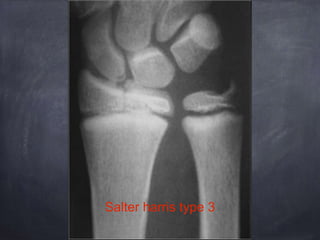

Salter harris classification

Salter harris type 3